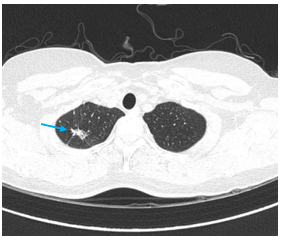

- Siêu âm hạch cổ: hạch bất thường thượng đòn 2 bên kích thước 8x15mm; không rõ cấu trúc rốn hạch

- Sinh thiết hạch thượng đòn phải dưới hướng dẫn của siêu âm cho kết quả:

Giải phẫu bệnh: Ung thư biểu mô di căn hạch

Hóa mô miễn dịch: Hình hình ảnh mô bệnh học và hóa mô miễn dịch phù hợp với ung thư biểu mô tuyến phổi di căn hạch; PDL-1 dương tính, TPS= 95%; EGFR (-); ALK (-)

- Siêu âm hạch cổ: không phát hiện bất thường

Hình 9: Hình ảnh siêu âm hạch cổ: không phát hiện bất thường